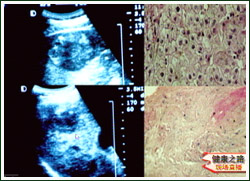

主持人:来看一段微波治疗的片子:首先用超声检查定位,阴影区域就是肝肿瘤的位置,消毒后进行局麻,然后用尖刀片在麻醉点切皮大约0.5厘米,再在超声引导下将穿刺针直接穿入肿瘤内,从右图中可以看到整个的进行过程,红色箭头所指就是穿刺针到达肿瘤的位置,在治疗的过程中局部滴冰水是为了防止皮肤烫伤,用超声监测就可以了解到治疗过程中的变化。

何文:来看这位患者的片子:在肝右部有一个9厘米的肝癌,治疗后肿瘤明显缩小,形成的薄膜可以限制肿瘤的扩散和转移,治疗后肿瘤区完全坏死,患者治疗后已经存活一年多了,正在随访过程中。

主持人:来看另外一位患者的情况:这位患者是突然肝癌破裂后到医院进行抢救,接受了微波治疗。患者:"去年6月14日我在家里拿花盆时觉得筋拽着脖颈,一直到肩膀,筋拽着疼,送到密云县医院后观察了四、五个小时,由于肝癌破裂大出血,流了6000多毫升血,经过输血抢救后在医院住了15天,以后做了微波治疗后感觉精神好多了,比较重的体力活儿完全可以干,胃口也很好。"何文:我们来看看对这位患者进行微波治疗的情况:如图肝脏的右叶有一个五乘六厘米的肝癌,治疗后肿瘤明显缩小,肿瘤区完全坏死,患者治疗后的各项指标都恢复了正常,说明对于这一类患者微波凝固治疗也是有效的。